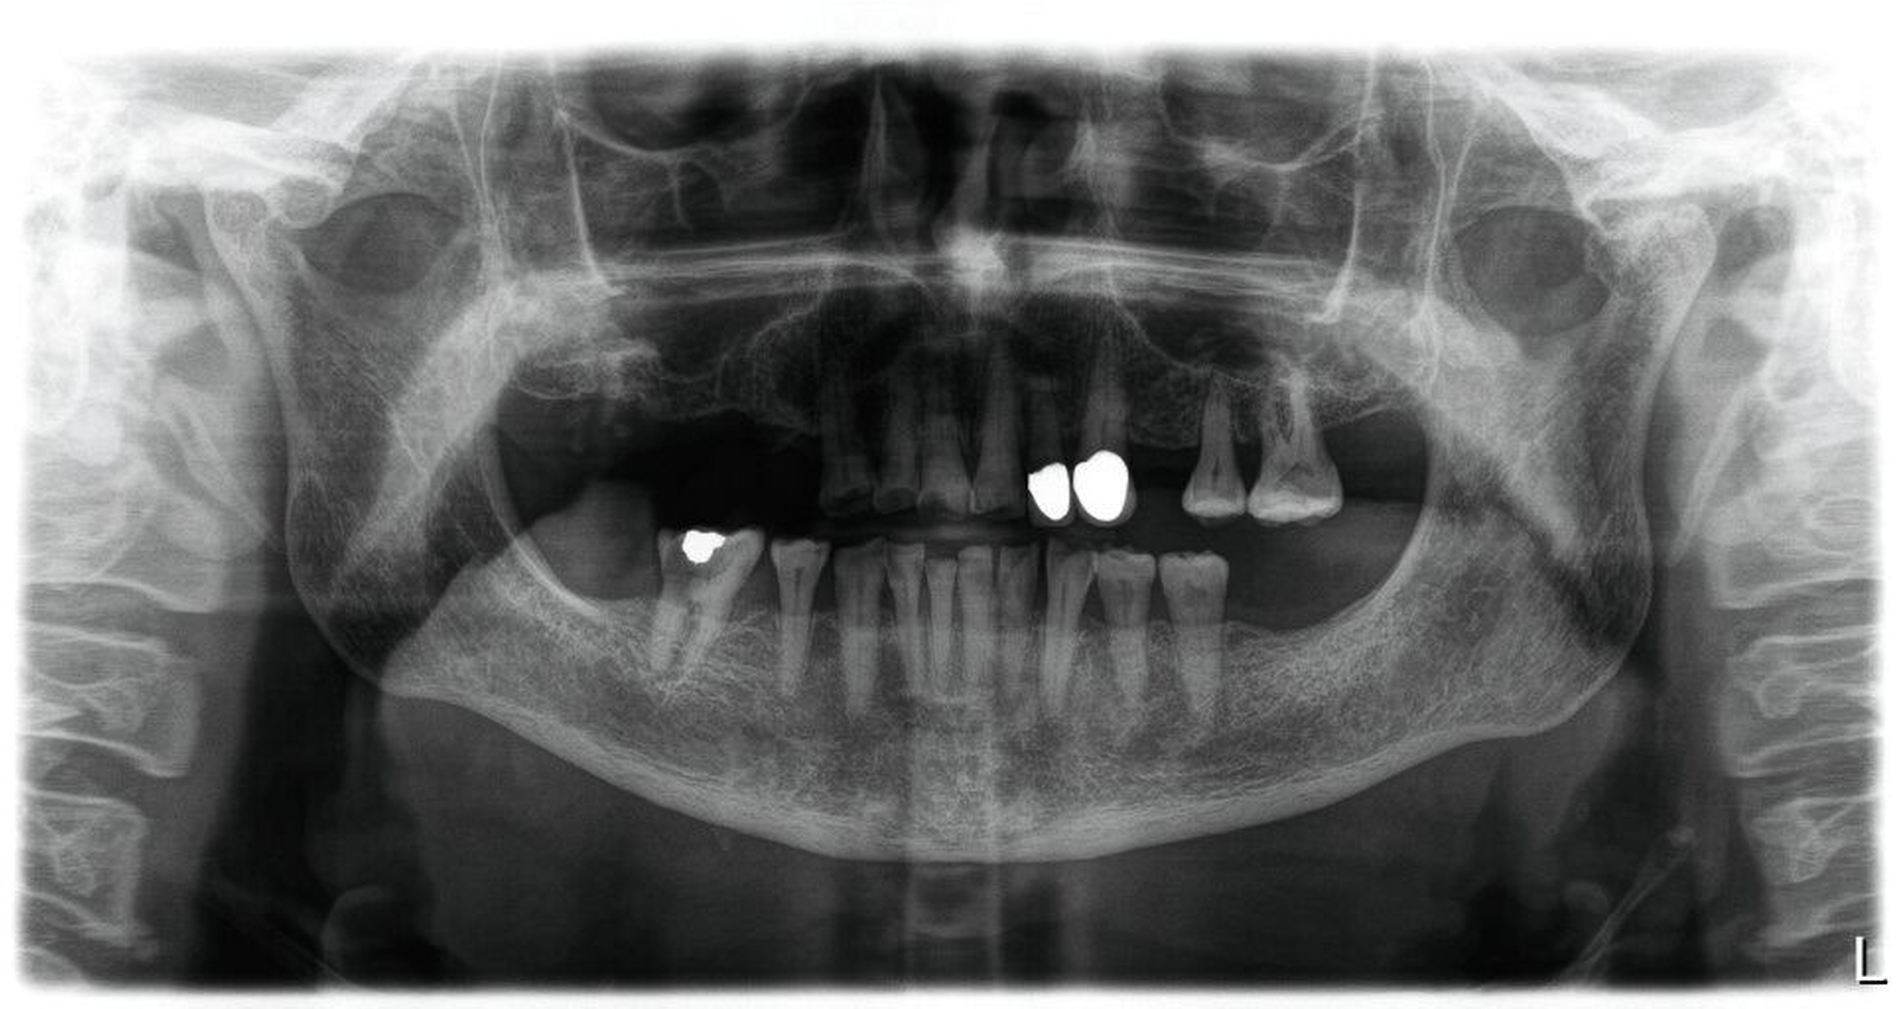

Beikler: Typisch sind häufig eine reduzierte Alveolarknochenhöhe und vor allem eine verminderte Alveolarknochendichte. In unseren eigenen zahnmedizinischen Analysen zeigten Hypophosphatasie-Patientinnen und -Patienten zudem niedrigere Mineralisationsgrade des Alveolarknochens im Vergleich zu Kontrollen, was diese radiologischen Eindrücke stützt. Zusätzlich kann die Lamina dura ausgedünnt, unklar oder insgesamt weniger eindeutig abgrenzbar erscheinen.

Auf Zahnebene können – teils im Zusammenhang mit Dentinmineralisationsstörungen – vergrößerte Pulpenkammern und Wurzelkanäle auffallen, bis hin zum Bild von „Shell teeth“. Zudem werden verkürzte und teils atypisch geformte Wurzeln beschrieben. Insgesamt sind all das Zeichen einer Hypomineralisation, die sich radiologisch sowohl am Knochen als auch an den Zahnhartsubstanzen zeigen kann. Wichtig ist die Einordnung: Diese bildgebenden Befunde sind für sich genommen nicht pathognomonisch, werden in Kombination mit der Klinik aber hochgradig wegweisend.

Sehr wichtig ist außerdem die saubere Dokumentation: Zahnverluste und orale Befunde sollten zeitnah mit Fotos und Röntgenbildern festgehalten werden. Und bei Verdacht sollte frühzeitig an eine interdisziplinäre Abklärung gedacht werden – idealerweise über Einrichtungen mit osteologischer und zahnmedizinischer Expertise, häufig an Universitätskliniken.